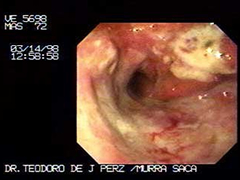

Paciente Masculino de 72 años:

Quien ha tenido larga historia y tratamientos multiples para dispepsia inicio sintomatología obstructiva por lo que consultan con medico general, quien inmediatamente me localiza vía telefónica para que le practicáramos este estudio. Extenso Carcinoma Gástrico que obstruye antro e infiltra extensamente el cuerpo y fondo.